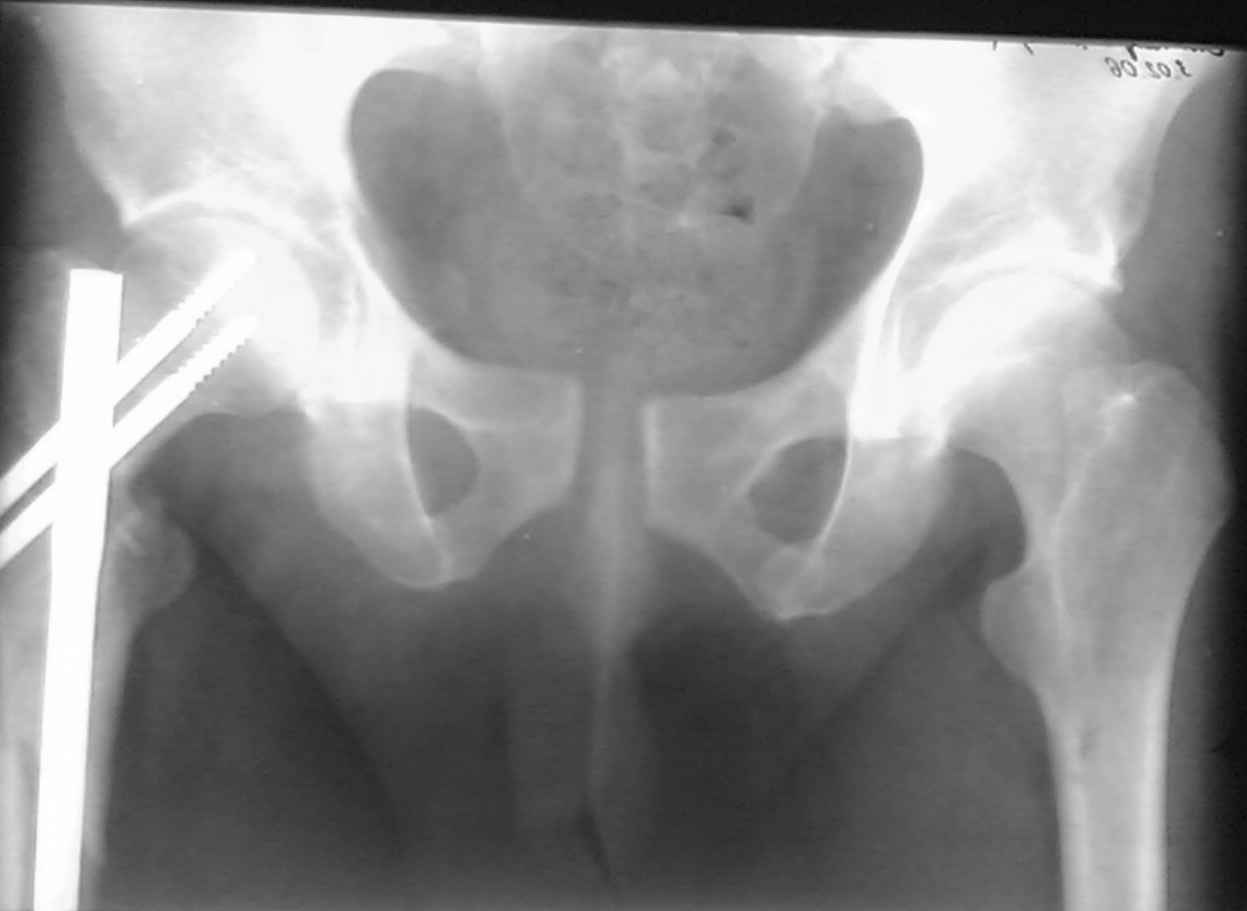

извините за опоздание , вот фотографии

<На R-мме таза ( в прямой проекции, вход и выход из таза) определяется изолированный разрыв лонного сочленения с диастазом 4см,расширение щели правого КПС(вертикальной нестабильности нет, >

В представленном случае повреждение несомненно ротационное и реальный диастаз как раз около пограничных 2,5 см, репозиция идеальная, достигнута в первые дни после травмы. Я бы ограничился 3 мес фиксации в аппарате с ограничением нагрузки первый месяц, и функциональными снимками в 6 -8 недель.